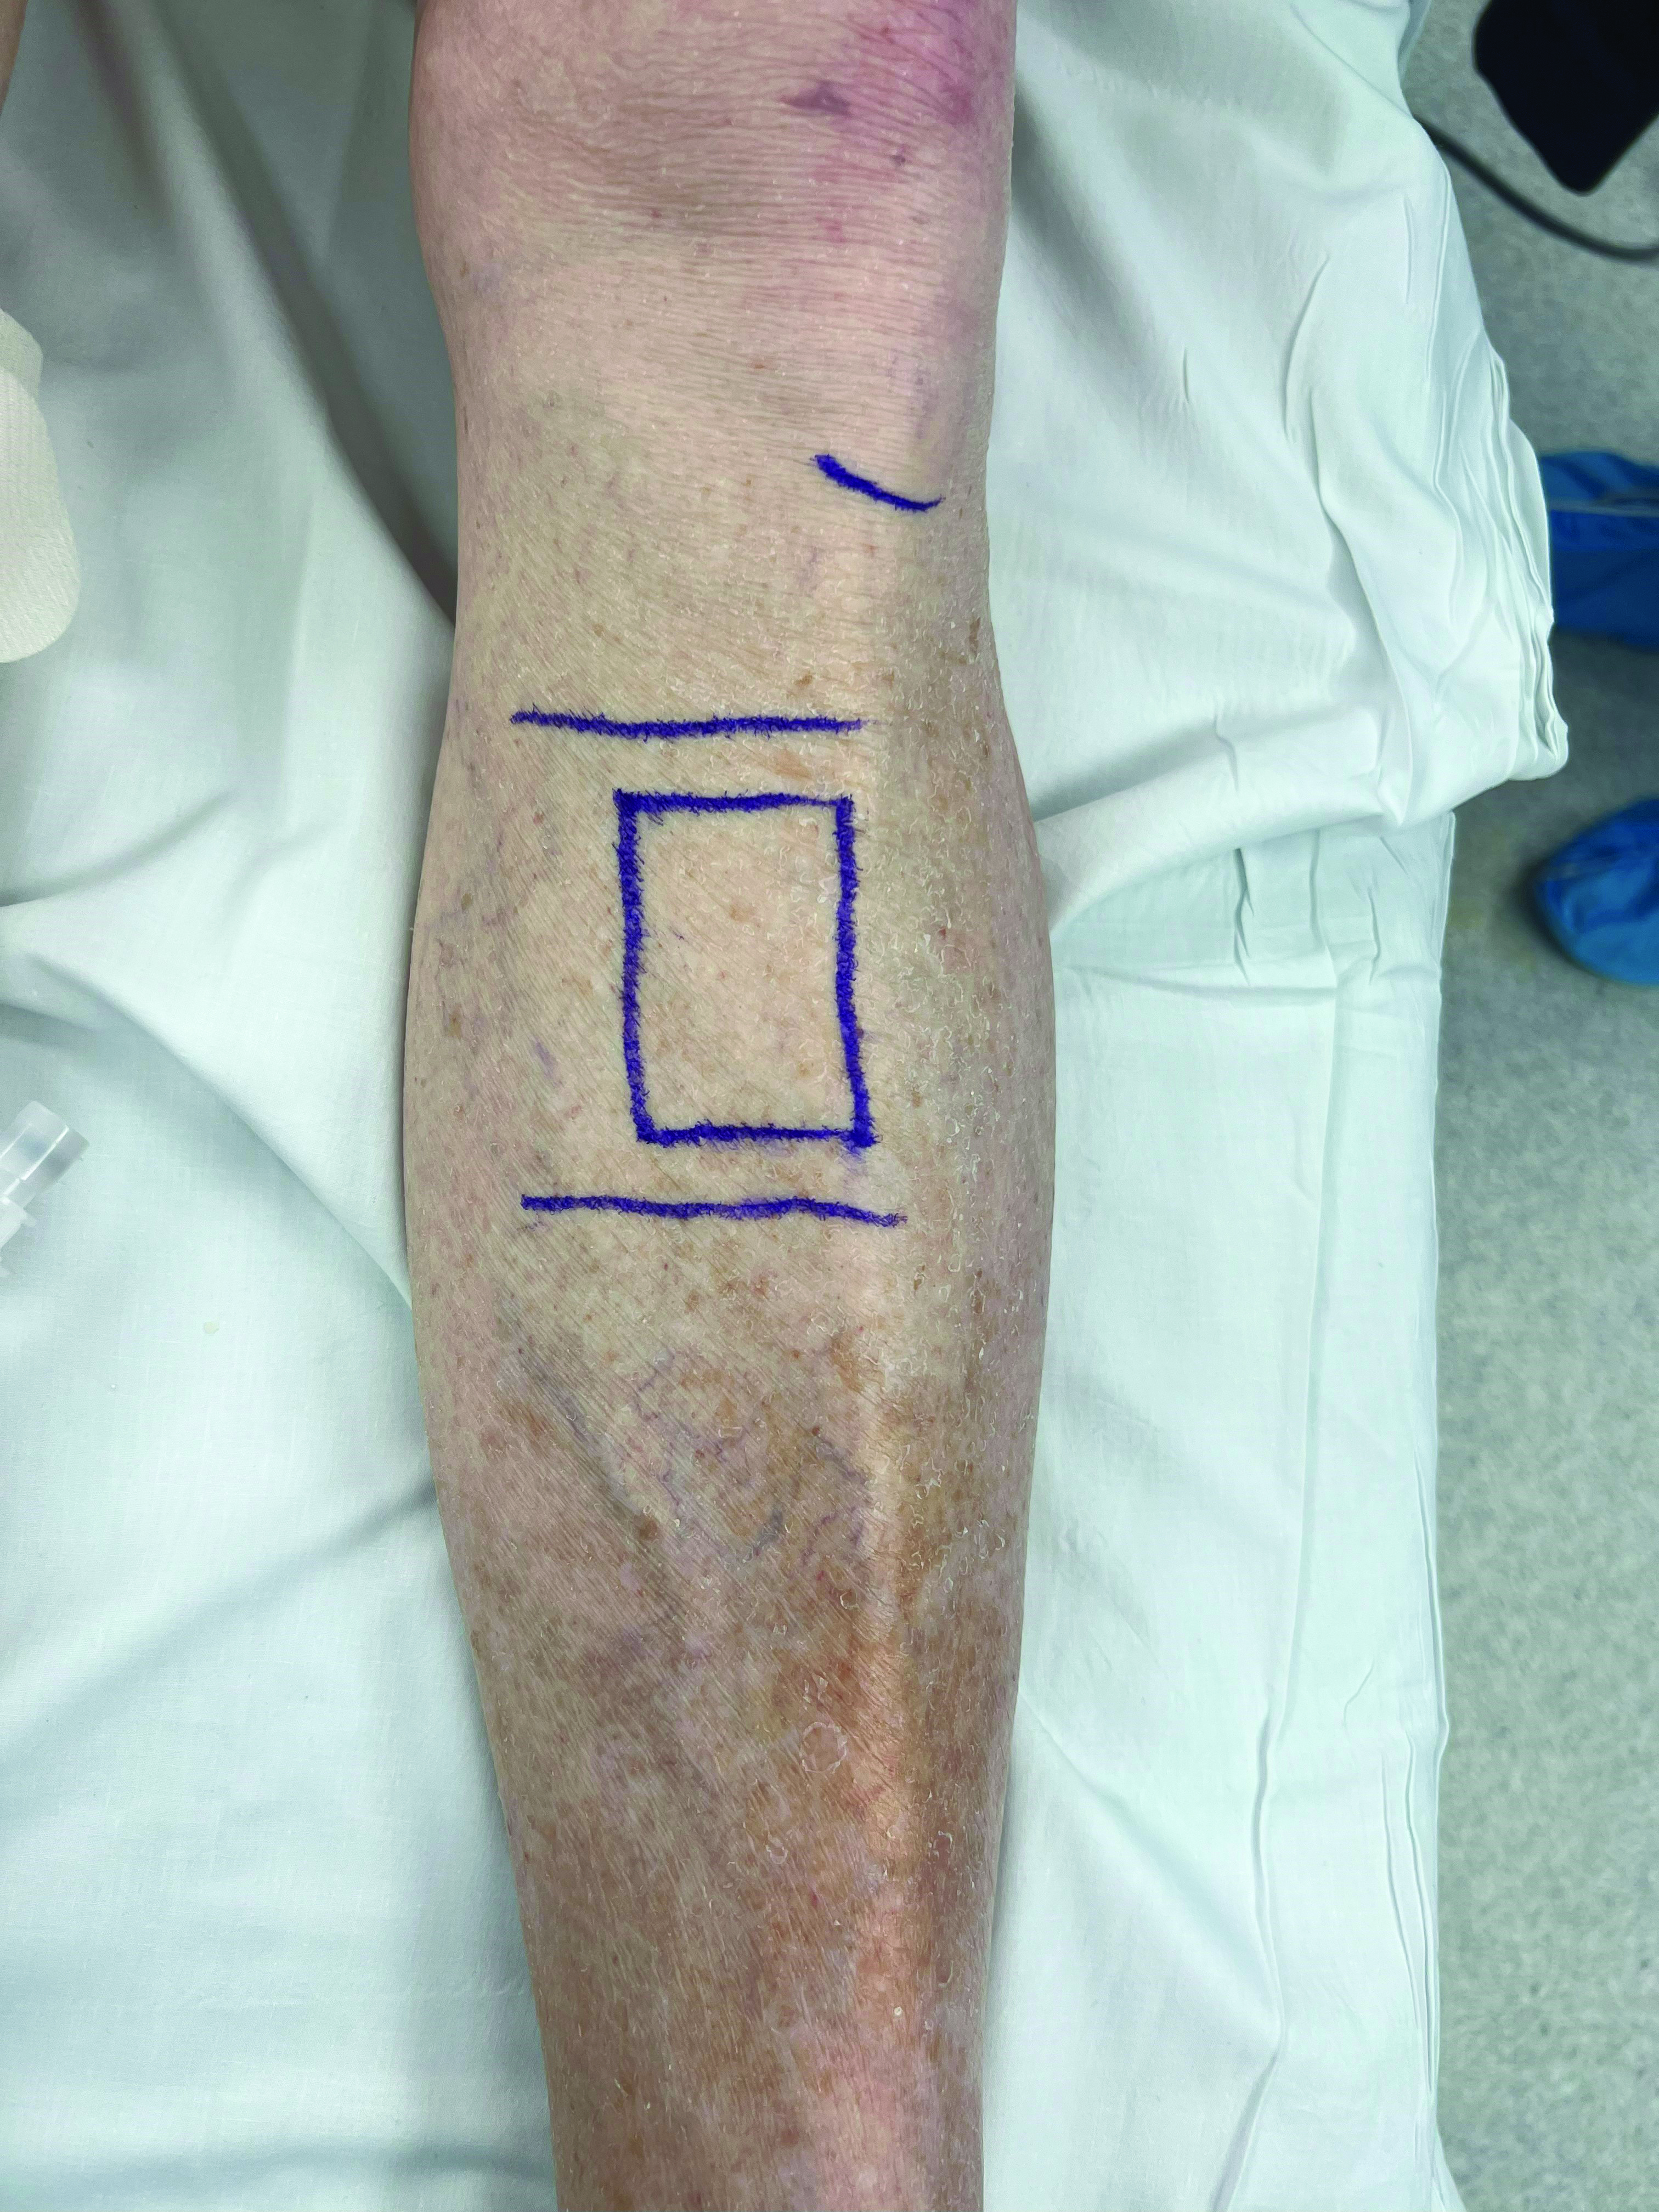

The surgeon confirms the planned placement of the distraction engine at the medial face of the tibia, approximately 3 cm distal to tibial tubercle, accounting for adding the proximal ring and the location of the fibular neck. The surgeon performs straightforward soft tissue dissection down to the periosteum, then introducing half pins within the planned osteotomy site prior to the corticotomy cuts to improve stability. The corticotomy then takes place with a sagittal saw to form a 5 cm x 2 cm unicortical bone window (Figure 1A-1D).

Alternatively, the surgeon may opt to perform the procedure percutaneously, which allows for minimal tissue handling. The half pins are secured percutaneously followed by creation of unicortical burr holes in a 5 cm x 2 cm formation that are then connected with a small osteotome via a minimally invasive technique to form the bone window (Figure series 2).